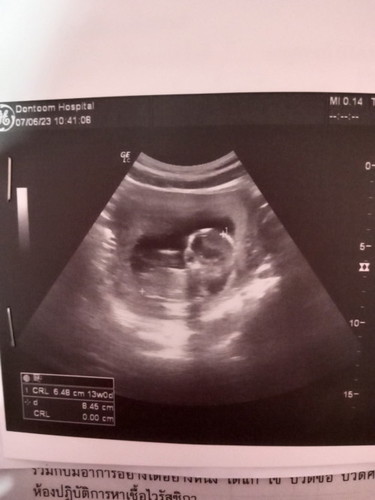

ตอนแรกซาว9w เจอแต่ถุงตั้งครรภ์ไม่เจอเด็ก หมอกลัวท้องลม วันนี้หมอนัดซาว เจอน้องแล้วจ้า ดีใจมาก ถ้าตามปจด.14w4d ตอนซาว หมอบอก13w